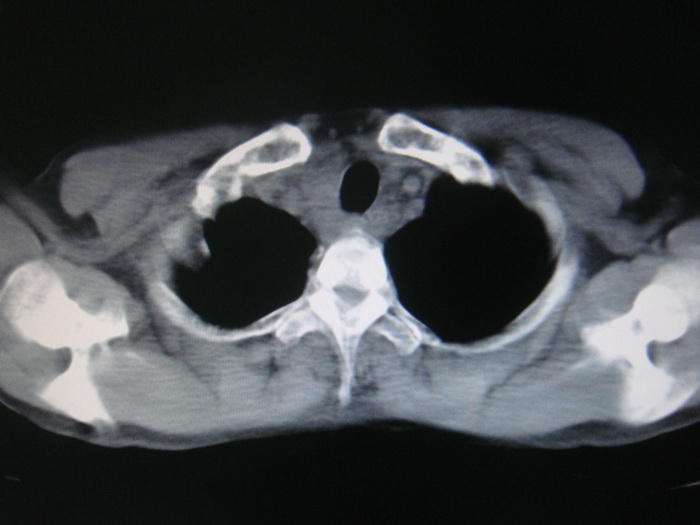

标题: CT28366:男性,45岁,偶尔发现右颈部肿块行胸部CT扫描。 [打印本页]

男性,45岁,偶尔发现右颈部肿块行胸部ct扫描。

两肺多发结节灶及纵膈淋巴结肿大考虑为转移

两肺多发性转移瘤,纵隔淋巴结转移。

颈部肿块也可能是转移。